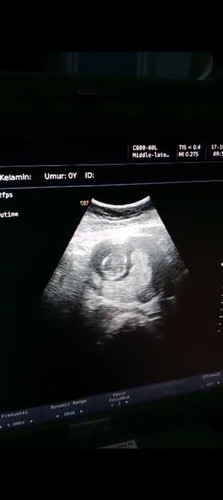

Usg 14 minggu apakah yg dibawah itu plasenta?

Apakah termaksud plasenta previa? Atau letak nya dibawah? Apakah bisa berubah🥺solusinya apa bund? Ovt bgt ini ##Sharing_dong_Bund #bantujawab #SeriusTanya #ingintahu

kata dokternya gimana bun? plasentanya dibawah atau gimana? aku alumni plasenta Previa total bun, di diagnosa pas usia 32 weeks untuk usia segitu udah kecil kemungkinannya untuk bergeser bun & kalo udah di diagnosa PPT (plasenta Previa total) itu harus bener bener bedrest jangan kecapean, stress nanti ngaruh ke bayinya, kalo usia 14 Minggu masih banyak kemungkinan untuk bergeser itu bun dengan seiringnya bertambah bbjnya

Baca lagisama bund aku juga plasenta Previa atau di bawah di jalan lahir, tapi kata dokter ini masih bisa lahiran normal, nanti juga plasenta bakalan naik ketika janin mulai membesar, kata dokter gausa khawatir sih tenang aja,, yg penting usg rutin sesuai anjuran dokter misalkan di tm1,tm2 dan tm3 bun.. aku juga sempet ovt..

Baca lagiEngga apa apa bund, saya hamil 15 minggu kata dokter plasenta di bawah masih wajar, nanti memastikannya harus 25 week keatas, blm bisa disebut plasenta previa, karna seiring berjalan waktu plasenta bisa mutar/ naik ya. Berfikir positif selalu🥰